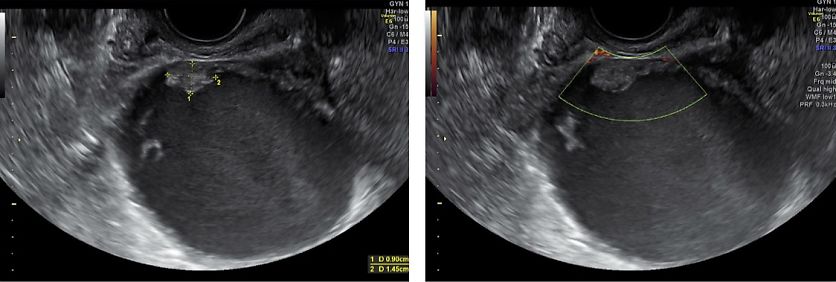

Ureters

Ureteral endometriosis (UE) is classified as extrinsic (fibrotic compression) or intrinsic (intraluminal infiltration), with extrinsic being more common.5 Although UE may be asymptomatic, it carries the risk of progressive hydronephrosis and renal damage. TVS can indirectly identify UE through visualization of hydronephrosis or ureteral dilatation (> 6 mm) and directly as a hypoechoic band or nodule compressing or deviating the distal ureter34 (Figure 13, Video 2).

The distal ureters can be identified laterally and posteriorly to the uterine arteries in the longitudinal plane. Deviation, thickening or reduced mobility of the ureter at this level should raise suspicion of UE involvement. Assessment of ureteral jets with color Doppler is recommended to confirm ureteral patency. In cases of hydronephrosis or loss of ureteric visualization, further imaging, such as renal ultrasound (Figure 14), computed tomography (CT) scan or MRI scan, should be considered.32

Both ureters and kidneys should be systematically evaluated in all patients with DE, particularly when sacrouterine ligament (SUL) or parametrial nodules are present. Ureteral involvement is often underestimated yet has significant surgical and functional implications.33,35

13

Parametrial fibrosis causing distal ureteral stenosis with proximal dilatation.